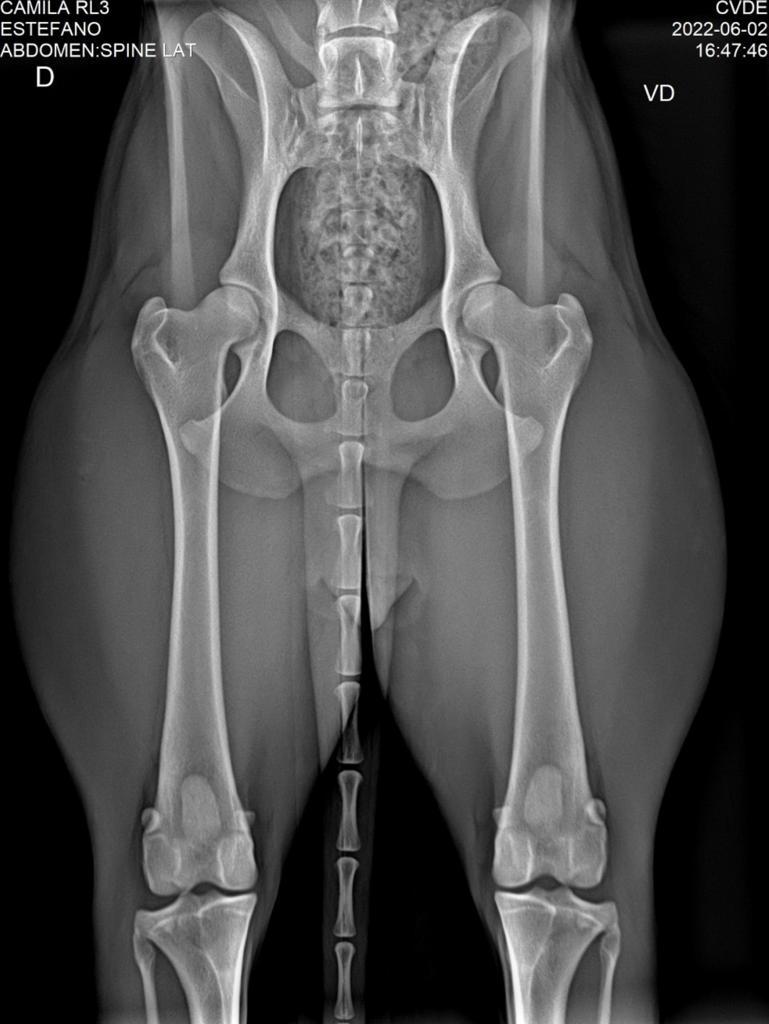

EXAME

DATA ANÁLISE

RESULTADO

LABORATÓRIO

DISPLASIA

02/06/2022

ADEQUADO GRAU A

VITRA TELERRADIOLOGIA VET.

LAUDO

CHAPA